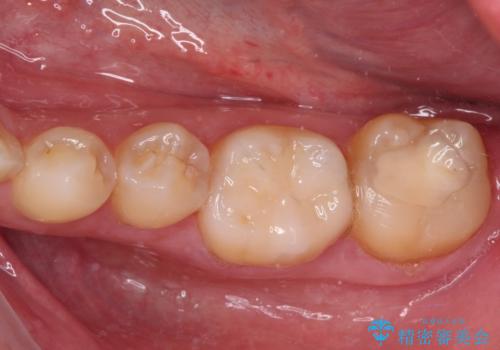

奥歯のむし歯が痛む セラミッククラウンとゴールドインレーによるむし歯治療